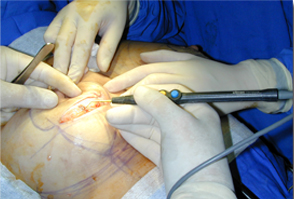

適用于細微、精細的切割如頭頸部,敏感部位皮膚的切割。

適合于皮下組織的切割和剝離。

特別是在運血較為豐富的部位。